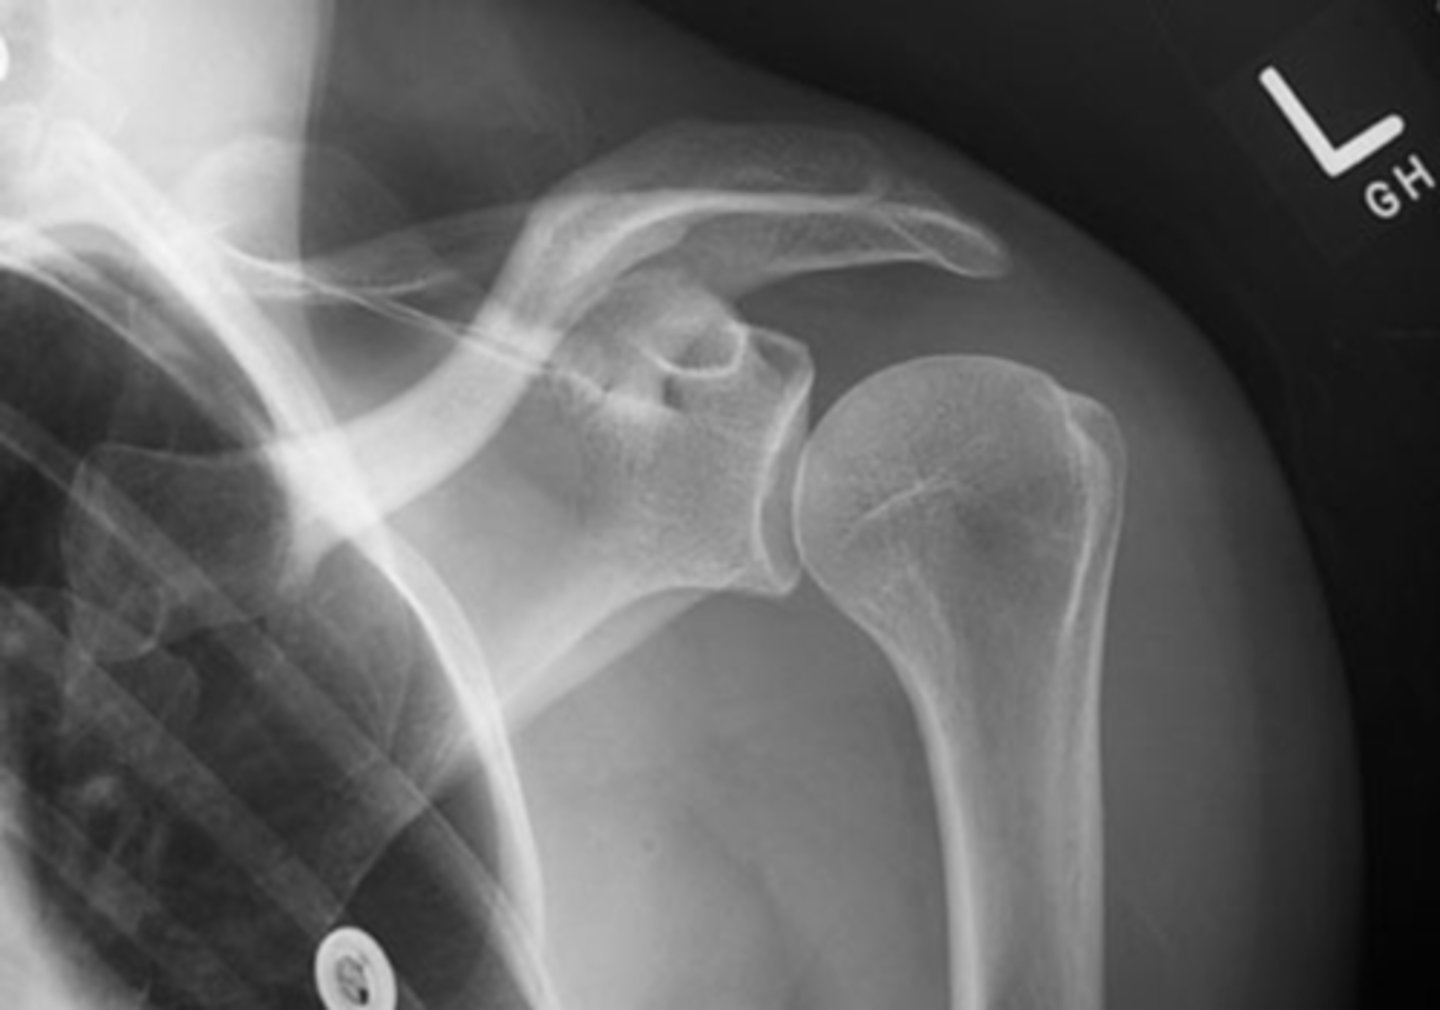

TRUE!!--we see healthy space b/w the clavicle and acromion, the humerus and the acromion, and b/w the glenoid and humerus...also, there is no sclerosing or osteophytes

True or false: this is a healthy GHJ